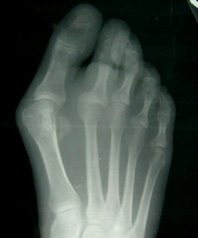

If the joint that connects your big toe to your foot has a swollen, sore bump, you may have a bunion. More than half the women in America have bunions, a common deformity often blamed on wearing tight, narrow shoes, and high heels. Bunions may occur in families, but many are from wearing tight shoes. Nine out of ten bunions happen to women. Nine out of ten women wear shoes that are too small. Too-tight shoes can also cause other disabling foot problems like corns, calluses and hammertoes.

With a bunion, the base of your big toe (metatarsophalangeal joint) gets larger and sticks out. The skin over it may be red and tender. Wearing any type of shoe may be painful. This joint flexes with every step you take. The bigger your bunion gets, the more it hurts to walk. Bursitis may set in. Your big toe may angle toward your second toe, or even move all the way under it. The skin on the bottom of your foot may become thicker and painful. Pressure from your big toe may force your second toe out of alignment, sometimes overlapping your third toe. An advanced bunion may make your foot look grotesque. If your bunion gets too severe, it may be difficult to walk. Your pain may become chronic and you may develop arthritis.

Typical Bunion |